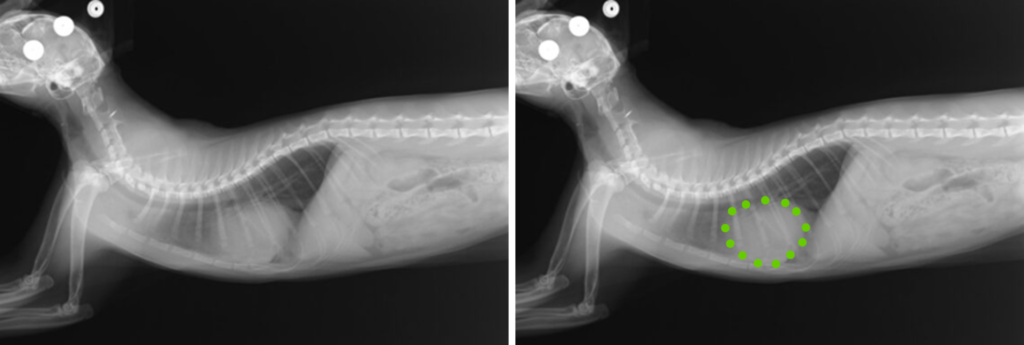

PPDHの診断には、胸部X線検査や超音波検査が有効であり、心膜腔内に腹部臓器が見られることで診断がつきます。場合によってはCT検査やMRIなどの高度画像診断も用いられ、他の胸腔内疾患との鑑別に役立ちます。

症例は、 スコティッシュフォールド、7か月齢、未避妊の女の子です。ヘルニアの整復を行うにあたり、避妊手術も同時に行いました。